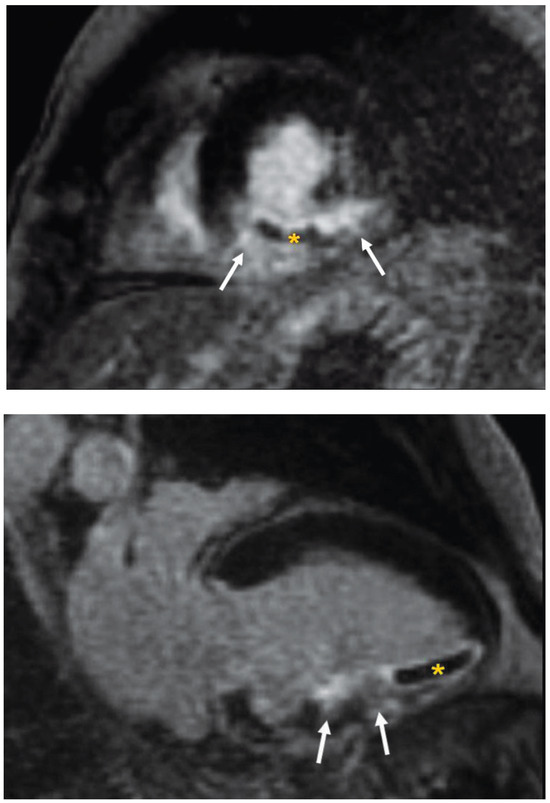

Intramyocardial Haemorrhage

by Stephan Schneiter and Andrew J. Taylor

Cardiovasc. Med. 2010, 13(5), 174; https://doi.org/10.4414/cvm.2010.01504 - 26 May 2010

A 59-year-old male patient presented with chest pain and electrocardiographic features of an acute inferolateral myocardial infarction [...] Full article